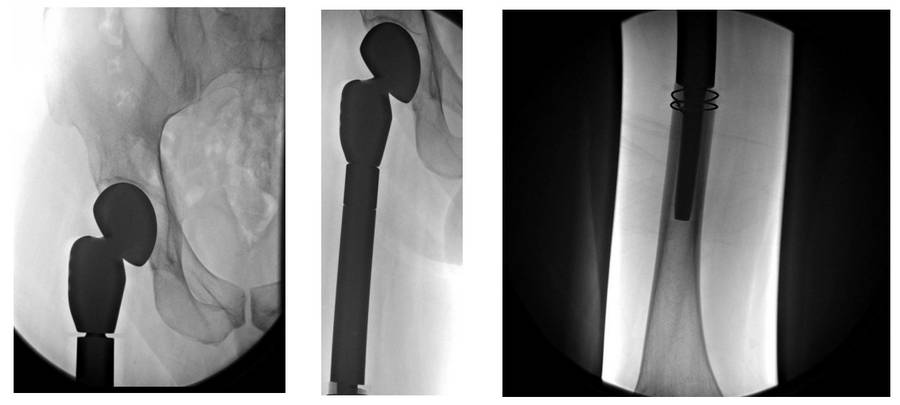

Before the surgery: X-ray shows a lytic lesion, and MRI shows an irregularly bordered heterogeneous mass with surrounding edema.

Post-Surgery: The X-ray shows the tumor prosthesis implanted after resection.